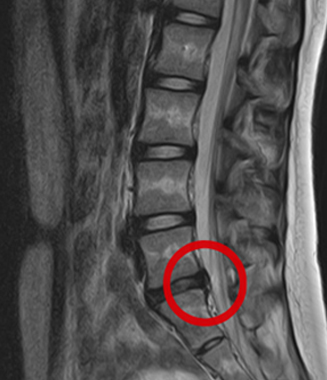

背骨を構成する1つ1つの骨を椎骨といいます、そのうち腰の部分にあるものが腰椎で、腰椎と腰椎の問にあってクッションの役目をしているのが椎間板です。椎間板の中心には髄核と呼ばれるゼラチン状のものがありますが、加齢とともに弾力性を失います。

この椎間板の周辺部分である線維輪の亀裂から、椎間板の中心部分である髄核が脱出し、神経を圧迫して、腰痛やお尻の痛み、足先に放散する痛み、シビレ、足に力が入らなくなった状態(いわゆる根性坐骨神経痛)を腰椎椎間板ヘルニアと言います。

令和4年夏頃、転倒したことをきっかけに腰痛と足の痺れが出現し、他院を受診されました。レントゲンおよびMRI検査にて「尾骶骨の異常」と「腰椎椎間板ヘルニア」と診断。 ブロック注射や鎮痛剤での治療を試みたものの効果がなく、根本解決を期待して「内視鏡下ヘルニア摘出手術」を受けられました。しかし、術後も痛みや痺れは全く改善せず、日常生活やお仕事に支障をきたしたまま、当院を受診されました。

今回のケースは、「MRIで見つかったヘルニアが、実は痛みの原因ではなかった」という、医療現場でしばしば起こる現象の典型例です。

実は、健康で腰痛が全くない人でも、MRIを撮ればヘルニアが見つかることは珍しくありません。S様の場合、転倒によって「仙腸関節機能障害」を引き起こしていましたが、偶然見つかったヘルニアが原因だと誤認され、手術が行われてしまったのです。

考察

AKA-博田法により症状が改善したことから、原因は腰椎椎間板ヘルニアではなく仙腸関節の機能障害であったと考えられます。仙腸関節は中腰をした際に機能障害を起こしやすくなります。ぎっくり腰も同様です。この方は症状改善後に再度MRIを撮りましたがヘルニアは治療前のMRIと変わりない状態でした。つまりヘルニアはあるがそれは痛みの原因ではなかったのです。手術をしても治る事はなかったでしょう。